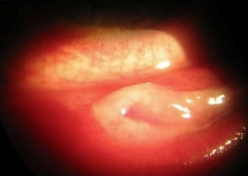

유행성 각결막염이 생기면 결막에 염증 막이 생길 수 있습니다. 다음 사진에서처럼요.

병원에 자주 다니시면서 이 막을 잘 제거하지 않으면 눈병이 낫고 나서 눈꺼풀과 눈알의 흰자위가 늘러붙을 수도 있습니다. 이렇게요..

이것을 검구유착이라고 합니다. 한번 생기고 나면 잘라내도 또 붙는 경우가 많습니다.